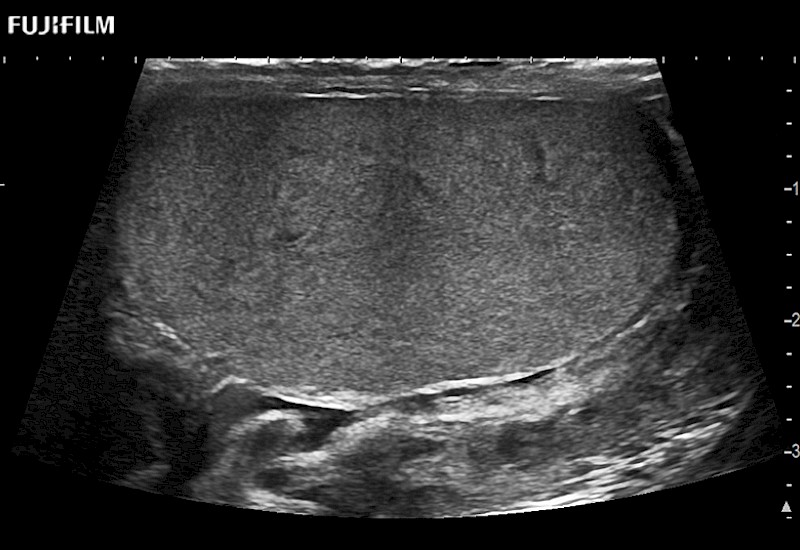

Abdominal transducer for biopsy, bladder and renal applications.

Main Specifications: